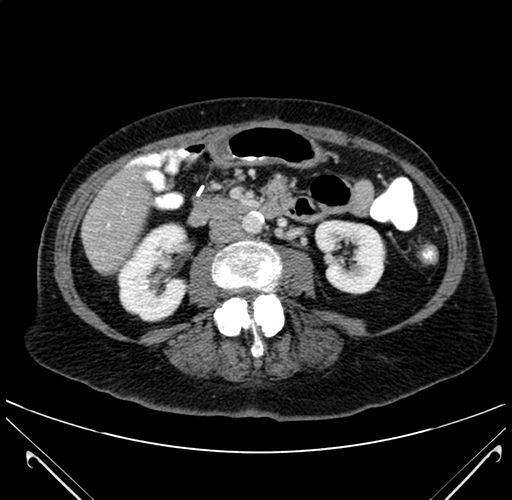

Axial Venous

Imaging analysis

Based on your CT findings, which issue(s) would give reason for "planned slowing down moment(s)" in this case?

Considering a standard right hepatectomy procedure, what step(s) of the operation would you do differently in this case?